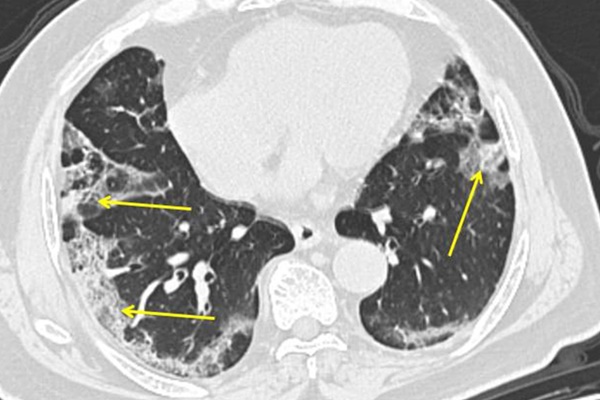

Trước đó, nhóm này đã giải mã thành công bộ gene của bệnh nhân nhiễm virus, vi khuẩn, nấm và ký sinh trùng. Loại bệnh truyền nhiễm gần giống với Covid-19 nhất mà nhóm này từng nghiên cứu là chứng viêm phổi do cúm nặng.